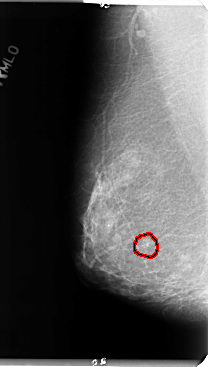

B_3124_1.RIGHT_MLO

RIGHT_MLO LINES 4760 PIXELS_PER_LINE 2696 BITS_PER_PIXEL 12 RESOLUTION 50 OVERLAY

FILE: B_3124_1.RIGHT_MLO.OVERLAY

TOTAL_ABNORMALITIES 1

ABNORMALITY 1

LESION_TYPE CALCIFICATION TYPE PLEOMORPHIC DISTRIBUTION CLUSTERED

ASSESSMENT 4

SUBTLETY 2

PATHOLOGY BENIGN

TOTAL_OUTLINES 1

BOUNDARY